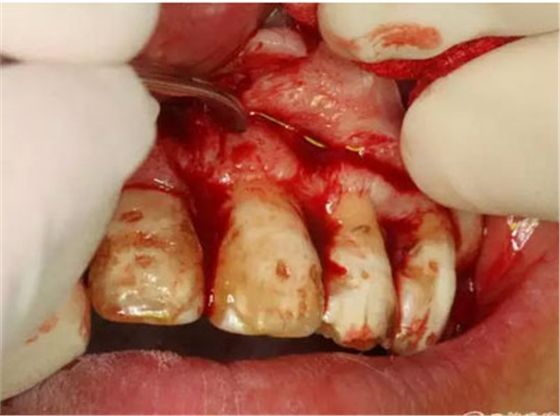

圖8.垂直切口+齦溝內(nèi)水平切口,水平切口延至23遠(yuǎn)中乳頭。

圖9.切口的交界處翻瓣,注意翻全厚瓣。